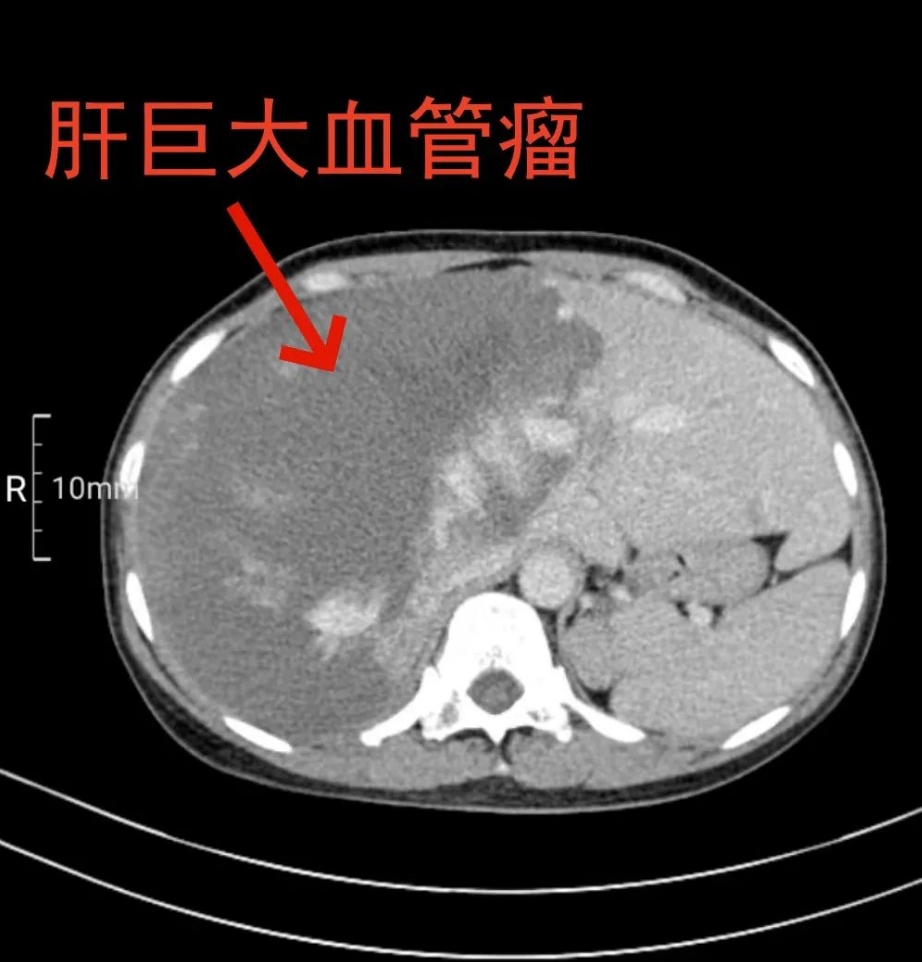

近日,我院肝胆外科团队为52岁的吴女士成功切除直径约24厘米,重达10余斤的巨大肝血管瘤。

据了解,吴女士2月前发现右上腹部可触及巨大质硬包块,伴有右上腹胀痛不适,呈逐渐加重趋势,尤其活动后右上腹部胀痛、坠胀感明显,并出现食欲减退,近1月体重减轻约10斤。外院检查示肝右叶巨大实性占位。吴女士被炸弹吓得不轻,这么大的血管瘤,万一破裂引起大出血,将会危及生命…… 当地医院建议吴女士手术治疗,但手术风险非常大,且术后可能出现肝脏衰竭等严重并发症。吴女士整日惶惶不安,经多方打听,辗转至我院肝胆外科就诊。

一切准备就绪后,刘兴贵带领肝胆外科负责人、副主任医师杨波,住院医师李俊阳,在麻醉科手术室团队的通力配合下,为吴女士行右半肝巨大血管瘤切除术。术中,可见血管瘤上至膈顶,向下压迫肾上腺,紧邻多处重要血管。他们仔细游离巨大肝血管瘤体病变组织,解剖第一肝门,处理患侧肝动脉、门静脉等重要结构,间歇阻断肝脏血流,沿着血管瘤边缘,精准地将直径长约24cm,重达10余斤的肝血管瘤完整切除。手术过程顺利。

杨波介绍,肝血管瘤是肝胆外科一种较为常见的肝脏良性肿瘤,临床上以海绵状血管瘤最多见。在医学上,直径10厘米以上的肝脏血管瘤被称为肝脏巨大血管瘤。手术切除是治疗肝海绵状血管瘤的有效方法。